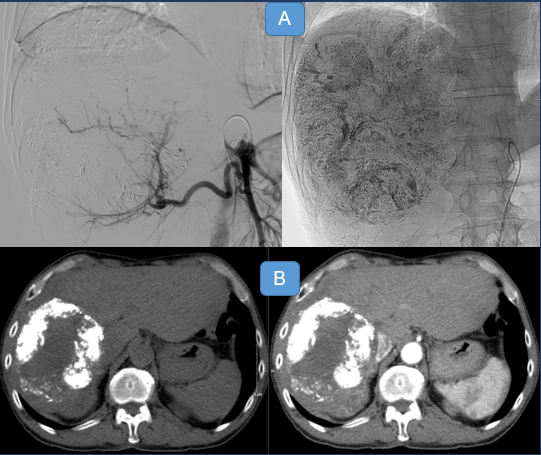

Hình 4: (A) khối u được nút mạch bằng cồn tuyệt đối. (B) Phần u được điều trị giảm kích thước, không còn ngấm thuốc.

BS. Trịnh Hà Châu: Nhiều nghiên cứu trên thế giới và thực tế tại Bệnh viện Bạch Mai cho thấy phương pháp này cho hiệu quả cao, tỷ lệ đáp ứng hoàn toàn và một phần cao, có những nghiên cứu cho thấy mức độ đáp ứng lên tới trên 70%. Đặc biệt với đặc tính hủy nội mô thành mạch, sự tái phát lại của các phần u đã điều trị thường rất thấp. Hơn nữa vật liệu sử dụng là cồn tuyệt đối cùng với lipiodol, giá thành thấp, lại phù hợp cho những khối u lớn (là vấn đề nan giải trong chi phí điều trị). Nút mạch u gan bằng cồn tuyệt đối là phương pháp an toàn, chi phí phù hợp đặc biệt với những khối u gan trung bình và lớn.